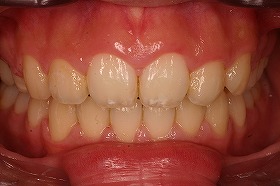

歯の矯正治療 症例ビフォー&アフター

この症例は、出っ歯を矯正治療でキレイにしたケースです。

しっかり噛んでいなかった前歯がかみ合うように並べました。

東京世田谷矯正歯科センターで、治療を進めると

出っ歯も後ろに下がり、噛み合わせもキレイになりました。

さらに上の歯が下の歯とあたるようになり、

とても食事がしやすくなったと喜んでいました。